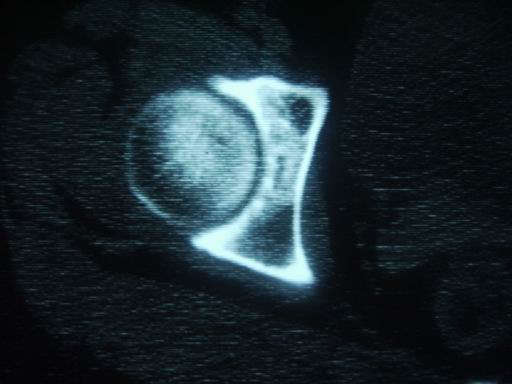

标题: CT19446:女性 右髋关节疼痛半年 近日加重 [打印本页]

标题: CT19446:女性 右髋关节疼痛半年 近日加重

没有外伤史那那种\"骨折\"一样的东西要怎么解释呢,可能是退变,囊变引起的,扫描有点厚,不利于连续层面观察,结核暂放弃

退变,关节软骨下囊变

考虑右髋关节退行性改变;不排除右侧髋臼慢性骨感染性病变。

考虑右侧髋臼慢性骨感染性病变。不除外关节软骨下囊变。